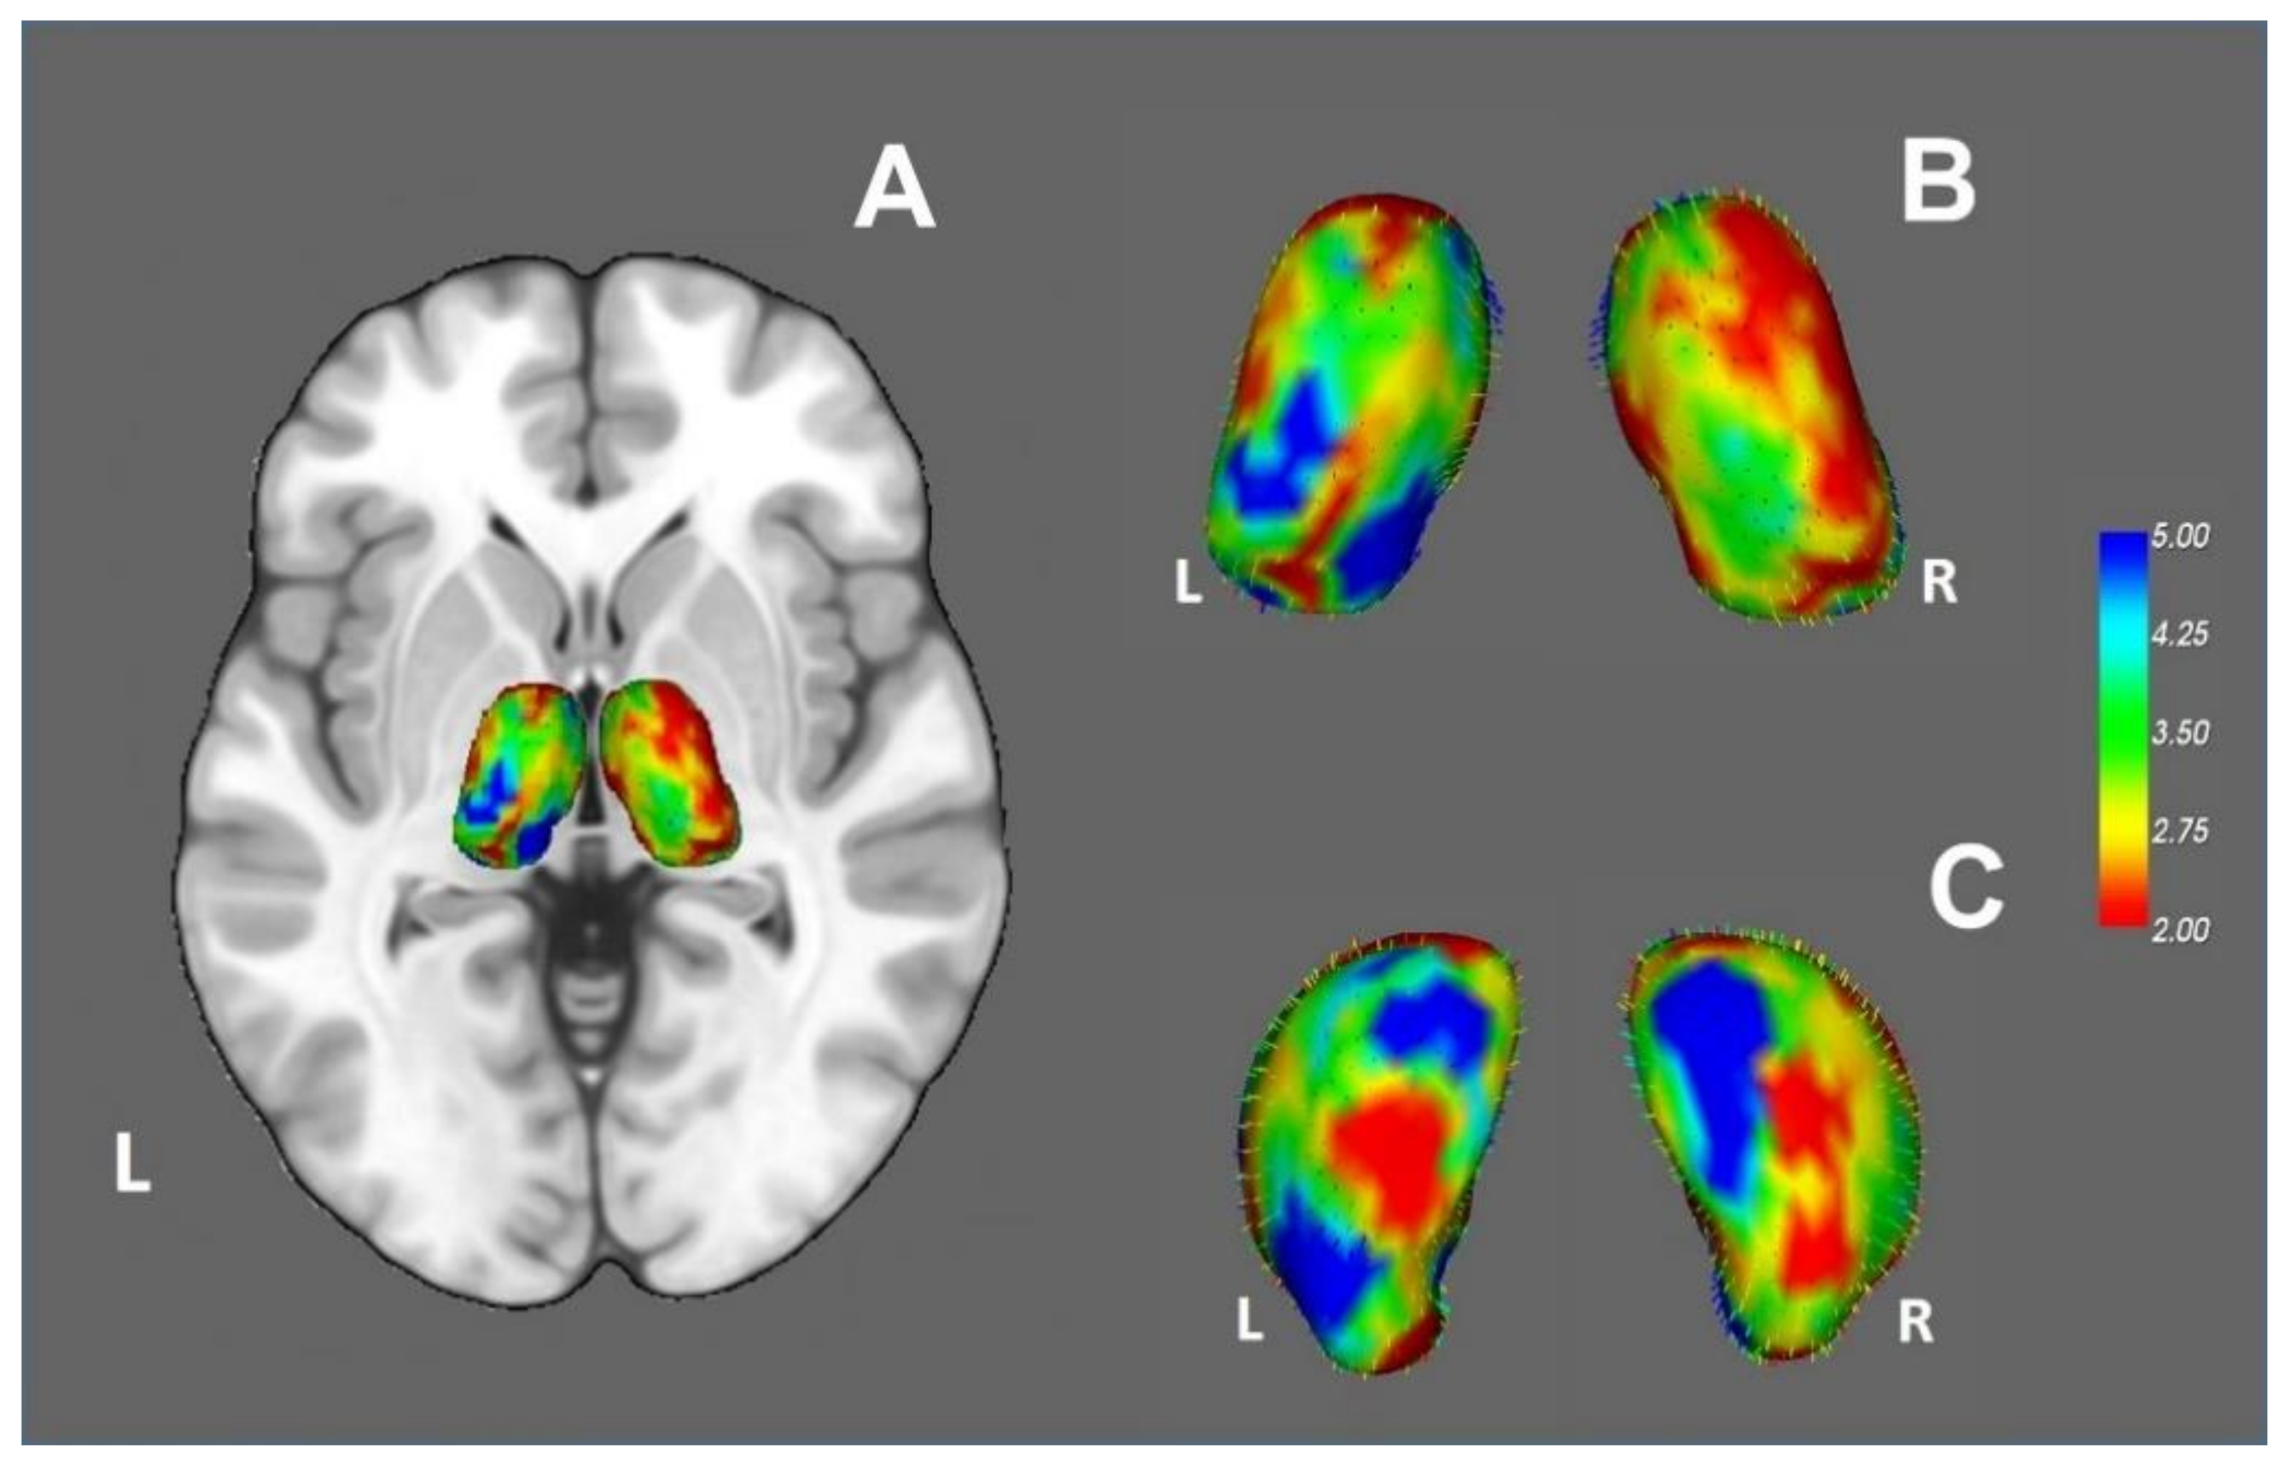

3.2.4. Vertex Analysis and Thalamic Parcellation